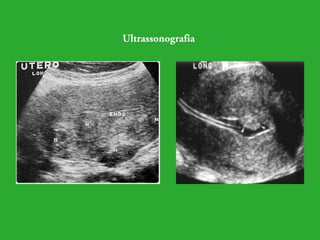

Os exames complementares para fazer o diagnóstico de leiomioma são

os seguintes: ultrassonografia, radiologia (com e sem contraste),

histeroscopia, laparoscopia, curetagem uterina, toque sob anestesia e

laparotomia, a ressonância é usada em casos excepcionais.

Ultrassonografia